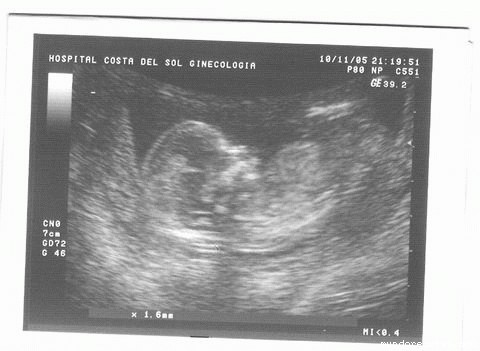

NO SE VE MUY BIEN PERO EN EL EC?GRAFO LO VIMOS PERFECTAMENTE. AUN NO SE VE SI ES ROSA O AZUL :lol: :lol: , PERO SE MUEVE UNA BARBARIDAD, DA CULAZOS Y SE PONE CABEZ ABAJO. LAS MANITAS CON SUS DEDITOS SE VEN MUY BIEN Y SE TOCABA A CARITA. EL PLIEGUE NUCAL Y LA LONGITUD DEL F?MUR SON NORMALES. TODO ESTÉ MUY BIEN!!! YA TENGO GANAS DE SABER SI SER? MACHOTE O PRINCESITA PERO HABR? QUE ESPERAR UN MES M?S.